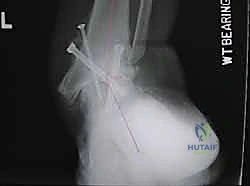

5. التثبيت بالبراغي القفلية (Locking Screws)

لضمان عدم تحرك المسمار أو دوران العظام حوله، يتم تثبيت المسمار ببراغي عرضية تخترق العظام والمسمار معاً من الأعلى (في الساق) ومن الأسفل (في الكعب والكاحل). يتم استخدام جهاز التصوير الإشعاعي (C-arm) داخل غرفة العمليات للتأكد من الموضع المثالي لكل مسمار.

6. إغلاق الجروح والتجبير

يتم إغلاق الشقوق الجراحية بعناية فائقة، وتوضع ضمادات معقمة، ثم يتم وضع الساق والقدم في جبيرة أو حذاء طبي صلب لحماية المنطقة ومنع أي حركة أثناء بداية الالتئام.